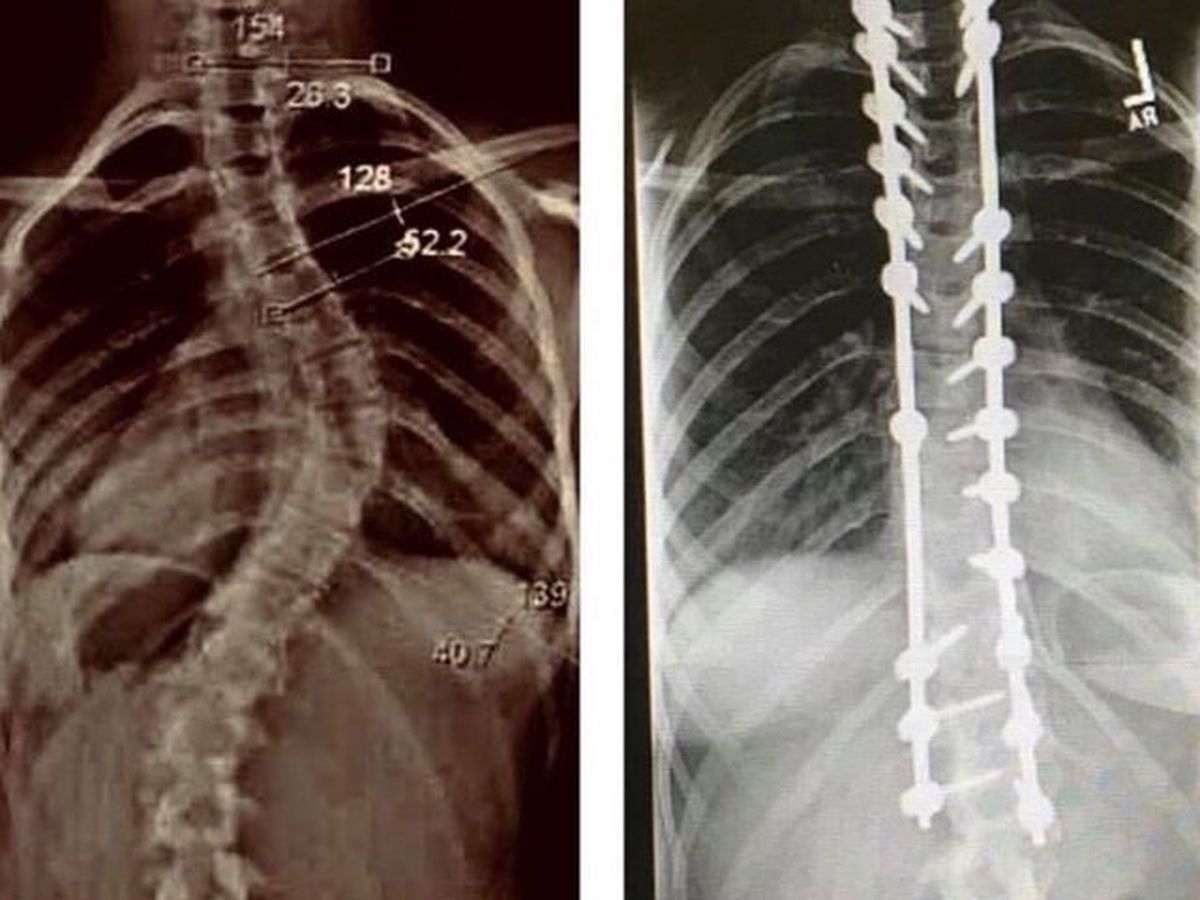

She's an amazingly brave, bad-ass. She's super creative and loves art. The last several years have thrown our family some curveballs that greatly affected Lesley especially. In 2015 Lesley was kicking butt in an all-boys soccer league, getting into volleyball, and about to start middle school, when a major growth spurt caused her to develop severe scoliosis. Not long after her diagnosis, her "Papaw," my father, whom Lesley was incredibly close to, committed suicide after a long struggle with his mental health. Lesley changed drastically. She stopped smiling, and stopped playing sports. She entered middle school the following year, withdrawn from her usual friends, and wearing a full, bulky, backbrace 22-hours a day, every day, in an effort to stop the growing curve in her spine. By 2017, she was really struggling, and asked to move in with her birth father, who had joined the military shortly after her birth and had not played much of a role in her life to that point. As a mother I was devastated, but I also saw that she was hurting, wanting to run from her grief, and looking for her dad to fill the void that my dad left. So, in December of 2017, she moved 20-hours away from all she had ever known, to El Paso, TX, to Fort Bliss Army base. By summer of 2018, the curve in her spine had grown to 60 degrees and was putting pressure on her lungs. Lesley underwent an 8-hour spinal fusion of more vertebrae than had ever been fused at once at the hospital in El Paso where her surgery was performed. She had 3 blood transfusions. I had flown to Texas for the surgery and to help with her recovery, and let me tell you, I have never seen someone so fierce. Her will to quickly recover and fight through the pain, was inspiring. She was incredibly proud of herself, as am I, and so happy to be free of the curve in her back. However, the severity of the curve had caused a very noticeable difference to one side of her developing chest, which was still slightly deformed from the twist. So, she continued to wear the baggy hoodies that once hid the hump on her back, to hide her chest. Her emotional wounds, however, after surgery and while still living with her father, began to heal. She continued to progress and mature. At the end of 2018 Lesley and her dad transferred to Fort Dix, an Army base in New Jersey. Lesley spent the following two Christmas and summer here at home, and in March of 2020, Lesley finally began to talk some about possibly coming back home for a while. On March 25th, 2020, Lesley called me hysterically begging for me to come get her. Naturally, I dropped everything and drove 10 hours to get my distressed baby, and as details further unfolded, Lesley disclosed tome that her father had given her sleeping medication that morning, and raped her. Since then we have lived a literal nightmare and participated in a stressful and lengthy investigation by the military, that has also uncovered several past victims. Empowering Lesley is my #1 priority, but I'm admittedly running short on my own mental and financial resources.